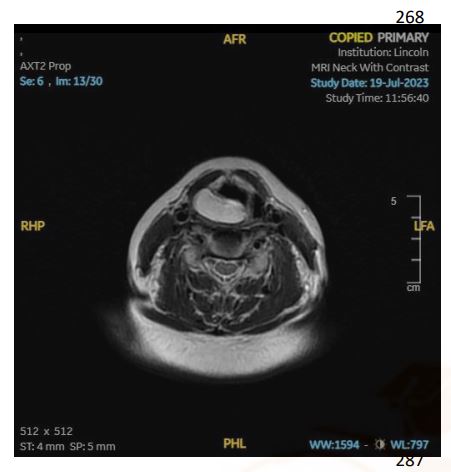

Transnasal flexible laryngoscopy revealed a large, round, and smooth mass situated over the right supraglottic area, covered by healthy mucosa. The origin of the mass could not be identified, and visualization of the vocal cords in their entirety was impeded due to the mass. A subsequent magnetic resonance imaging (MRI) scan of the neck with contrast delineated a well-defined, non-enhancing, fat-containing lesion in the right supraglottic region and was reported as measuring 2.9 cm in its widest dimension (see Figures 1B & 1C).